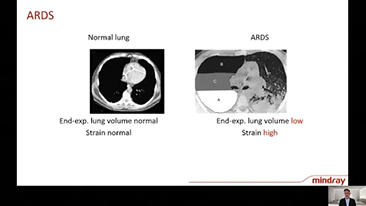

Door het diepgaande inzicht in de klinische behoeften van zowel pati?nten als zorgverleners, ondersteunen Mindray-beademingsapparaten de vereiste sequenti?le therapie bij zuurstoftherapie, niet-invasieve beademing en invasieve beademing met stabiele prestaties, veelzijdige functionaliteit en gebruiksgemak. Beademingsmodi en besluitvormingstools zijn ontwikkeld op basis van klinische behoeften en professionele richtlijnen, zodat medisch personeel rustig klinische beslissingen kan nemen voor alle pati?ntenpopulaties en alle ernstniveaus.

Het kiezen van de juiste beademingsinstellingen voor de behandeling van pati?nten met aandoeningen van de luchtwegen is een vrij belangrijke kwestie. Aangezien de taak van het specificeren van de parameters van beademingsapparatuur volledig wordt uitgevoerd door een arts, heeft de kennis en ervaring van de arts bij de selectie van deze instellingen een direct effect op de nauwkeurigheid van zijn/haar beslissingen. Het paradigma van de ondersteunende zorg voor pati?nten is in de afgelopen 20 jaar sterk veranderd. Tegenwoordig zijn er verschillende beademingsmodi en beslissingsondersteunende hulpmiddelen ontwikkeld rond klinische behoeften om zorgverleners te helpen effici?nter te werken en fouten bij klinische beslissingen te voorkomen.

De beademingsapparaten van de 3-in-1 SV Series integreren zuurstoftherapie met hoge flow, non-invasieve beademing en invasieve beademing voor stabiele prestaties, veelzijdige functionaliteit en gebruiksgemak. Uitzonderlijke longbeschermende eigenschappen en veel tools voor besluitvorming ontworpen om het risico op kruisbesmetting te verminderen en de dagelijkse last van zorgverleners te verlichten.